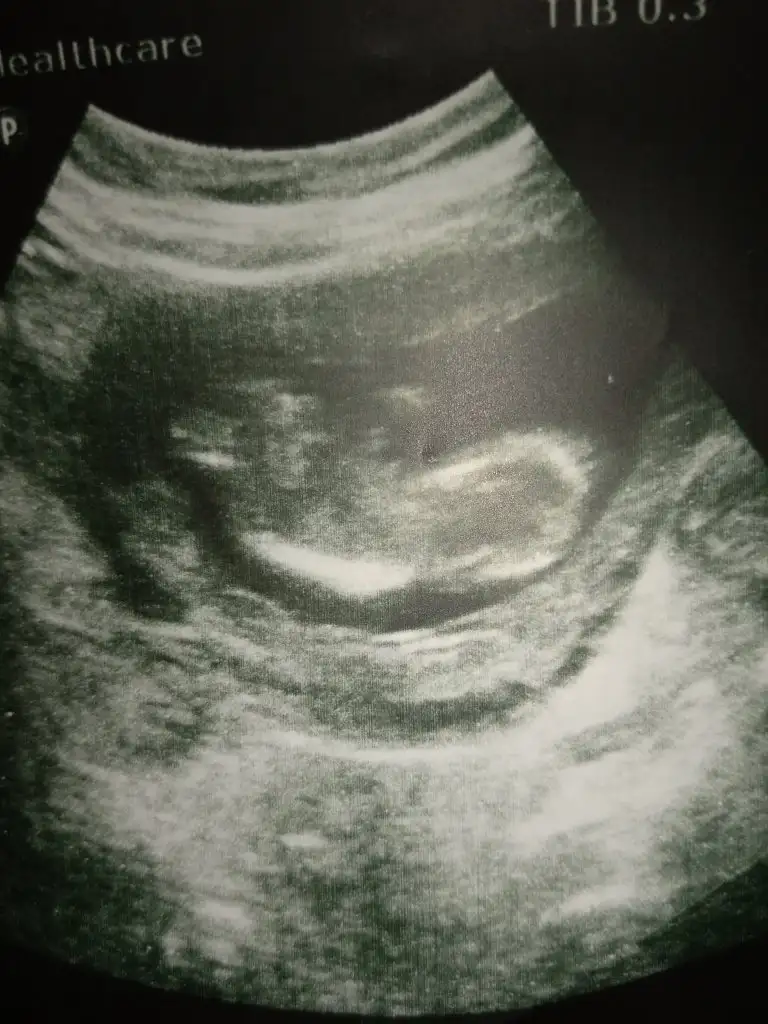

Kizz :)Bir başka ultrason istemiştiniz bunlar var elimde bacaklarini bağlamışti öylece duruyorduheyecanla yorumunuzu bekliyorumm Ikra meyra

Çok net değil usg ler sanki kız gibi ama emin değilim ☺Bunlar dan belli olurmu acaba biraz ultrason fotolarından şansımız yok ama kısmet artık☺

Ilk koydugum erkek altdaki koydugum kiz